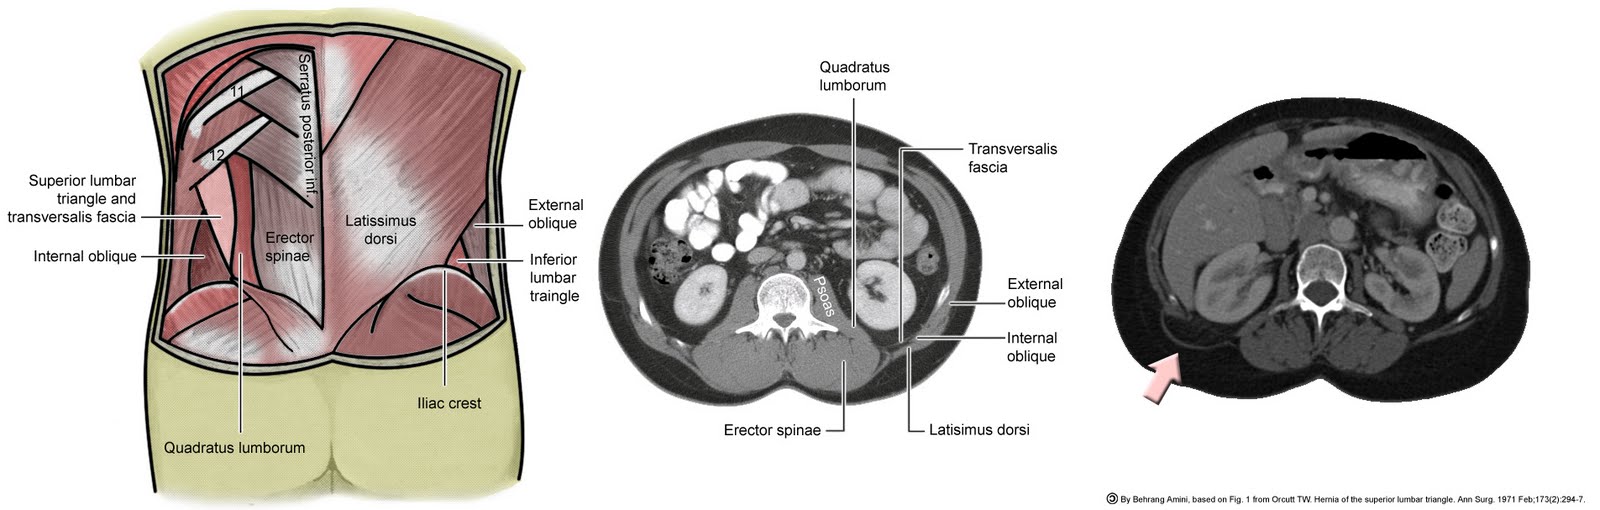

(a) The superior lumbar triangle bordered by the 12th rib, internal Lumbar Hernia Grynfeltt lumbar hernias occur through defects in the lumbar muscles or the posterior fascia, below the 12 th rib and above the iliac crest. grynfeltt's lumbar hernia is a rare abdominal wall pathology with around. the aim of the study was to describe the transabdominal laparoscopic. Lumbar Hernia Grynfeltt.

lumbar hernias occur through defects in the lumbar muscles or the posterior fascia, below the 12 th rib and above the iliac crest. the aim of the study was to describe the transabdominal laparoscopic. grynfeltt's lumbar hernia is a rare abdominal wall pathology with around.